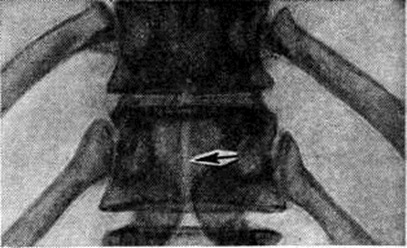

Рис. 4.

Рентгенограмма части грудного отдела позвоночника при незаращении заднего участка дуги с отсутствием остистого отростка (прямая проекция): зона незаращения заднего участка дуги указана стрелкой.